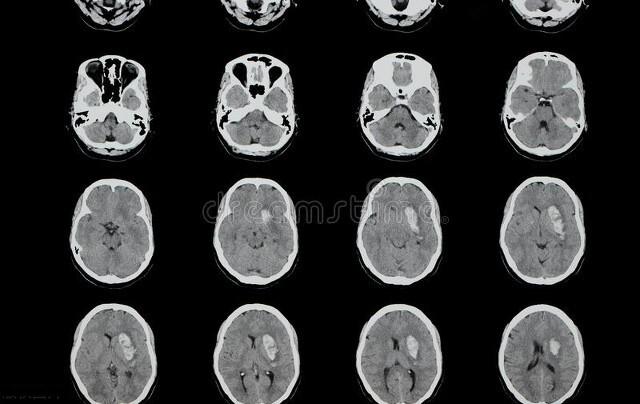

脑出血是一种致死率极高的疾病。根据“中国脑出血诊治指南(2019)”的统计,在我国,每10万人中,每年有12-15例的脑出血,30天病死率在35-52%,仅有约20%的病人在30天内恢复生活自理能力。然而,许多人并不知道,一些看似无害的日常习惯,却可能悄悄增加脑出血的风险。